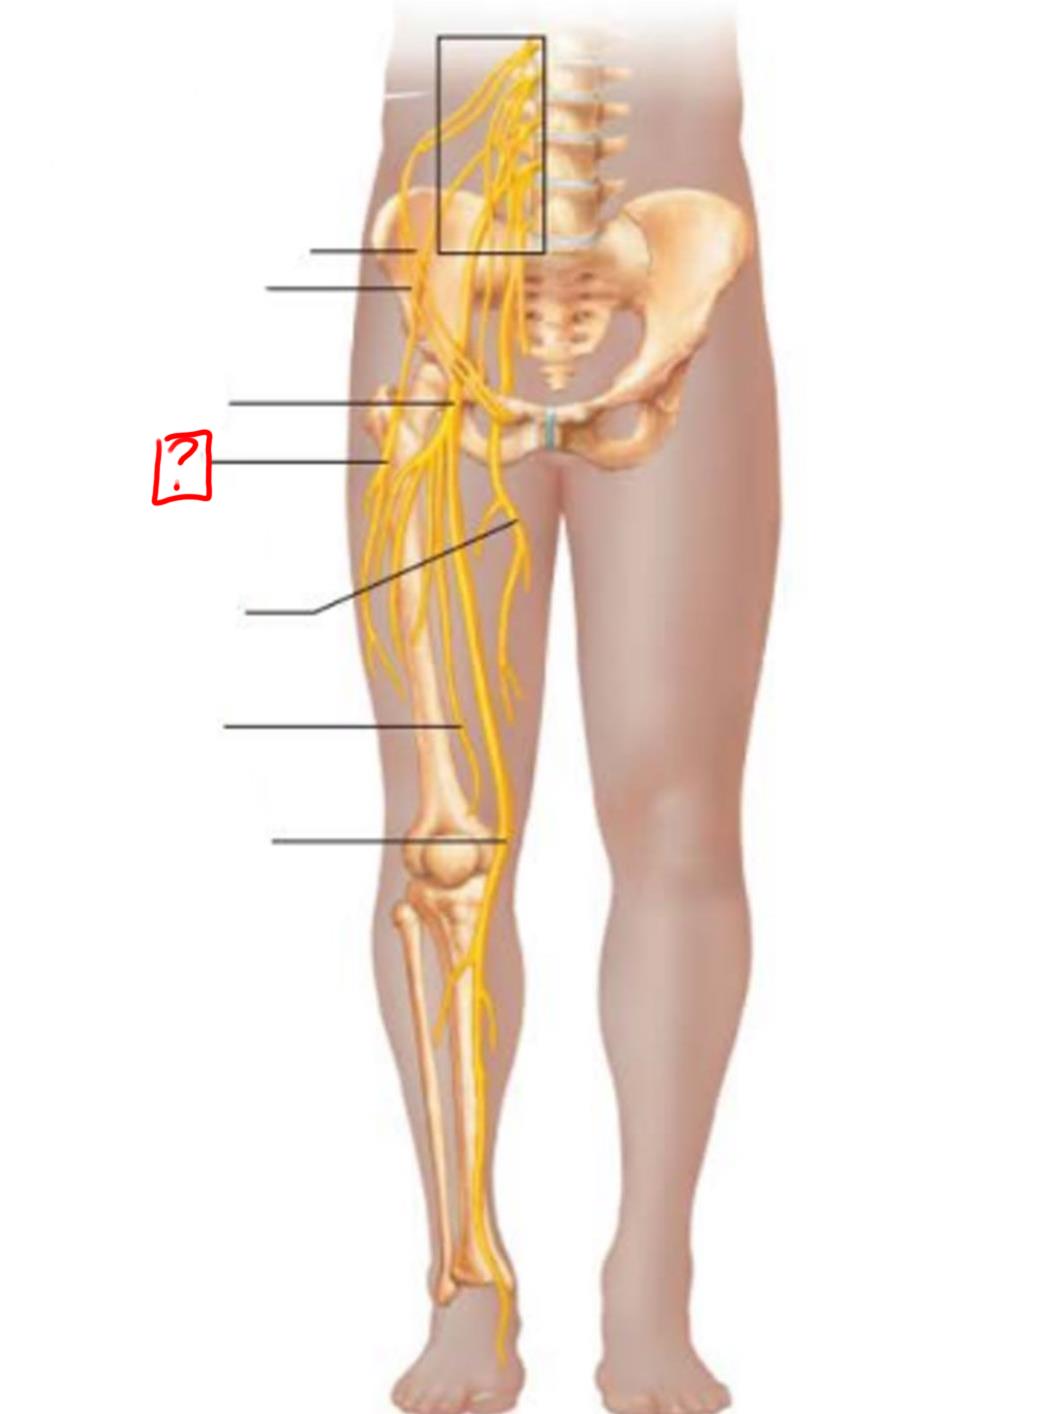

common fibular

tibial nerve

sural (cut)

deep fibular

superficial fibular

plantar branches

superior gluteal

lumbosacral trunk

inferior gluteal

common fibular

tibial

posterior femoral cutaneous